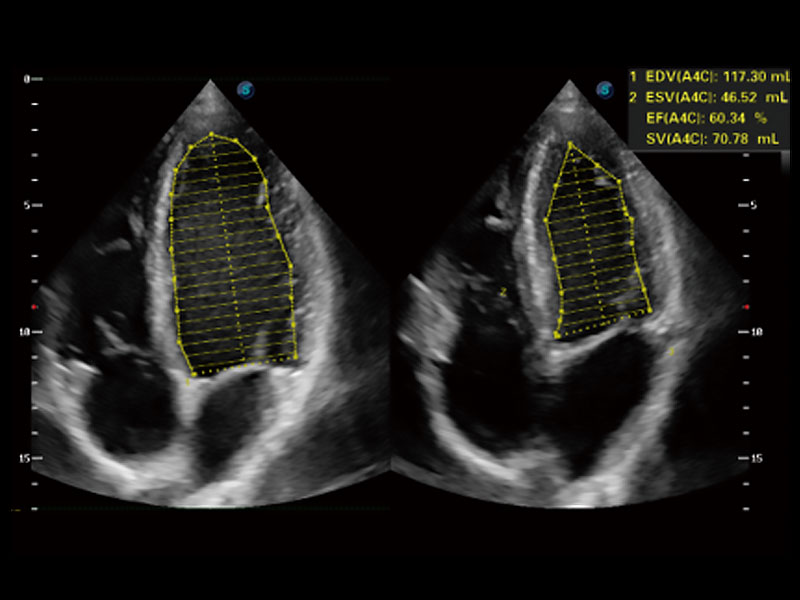

能夠基于左心室壁追蹤和辛普森法,自動計算射血分?jǐn)?shù),支持多個可移動點描跡,與手動測量相比,極大節(jié)省了動物醫(yī)生的時間和精力。